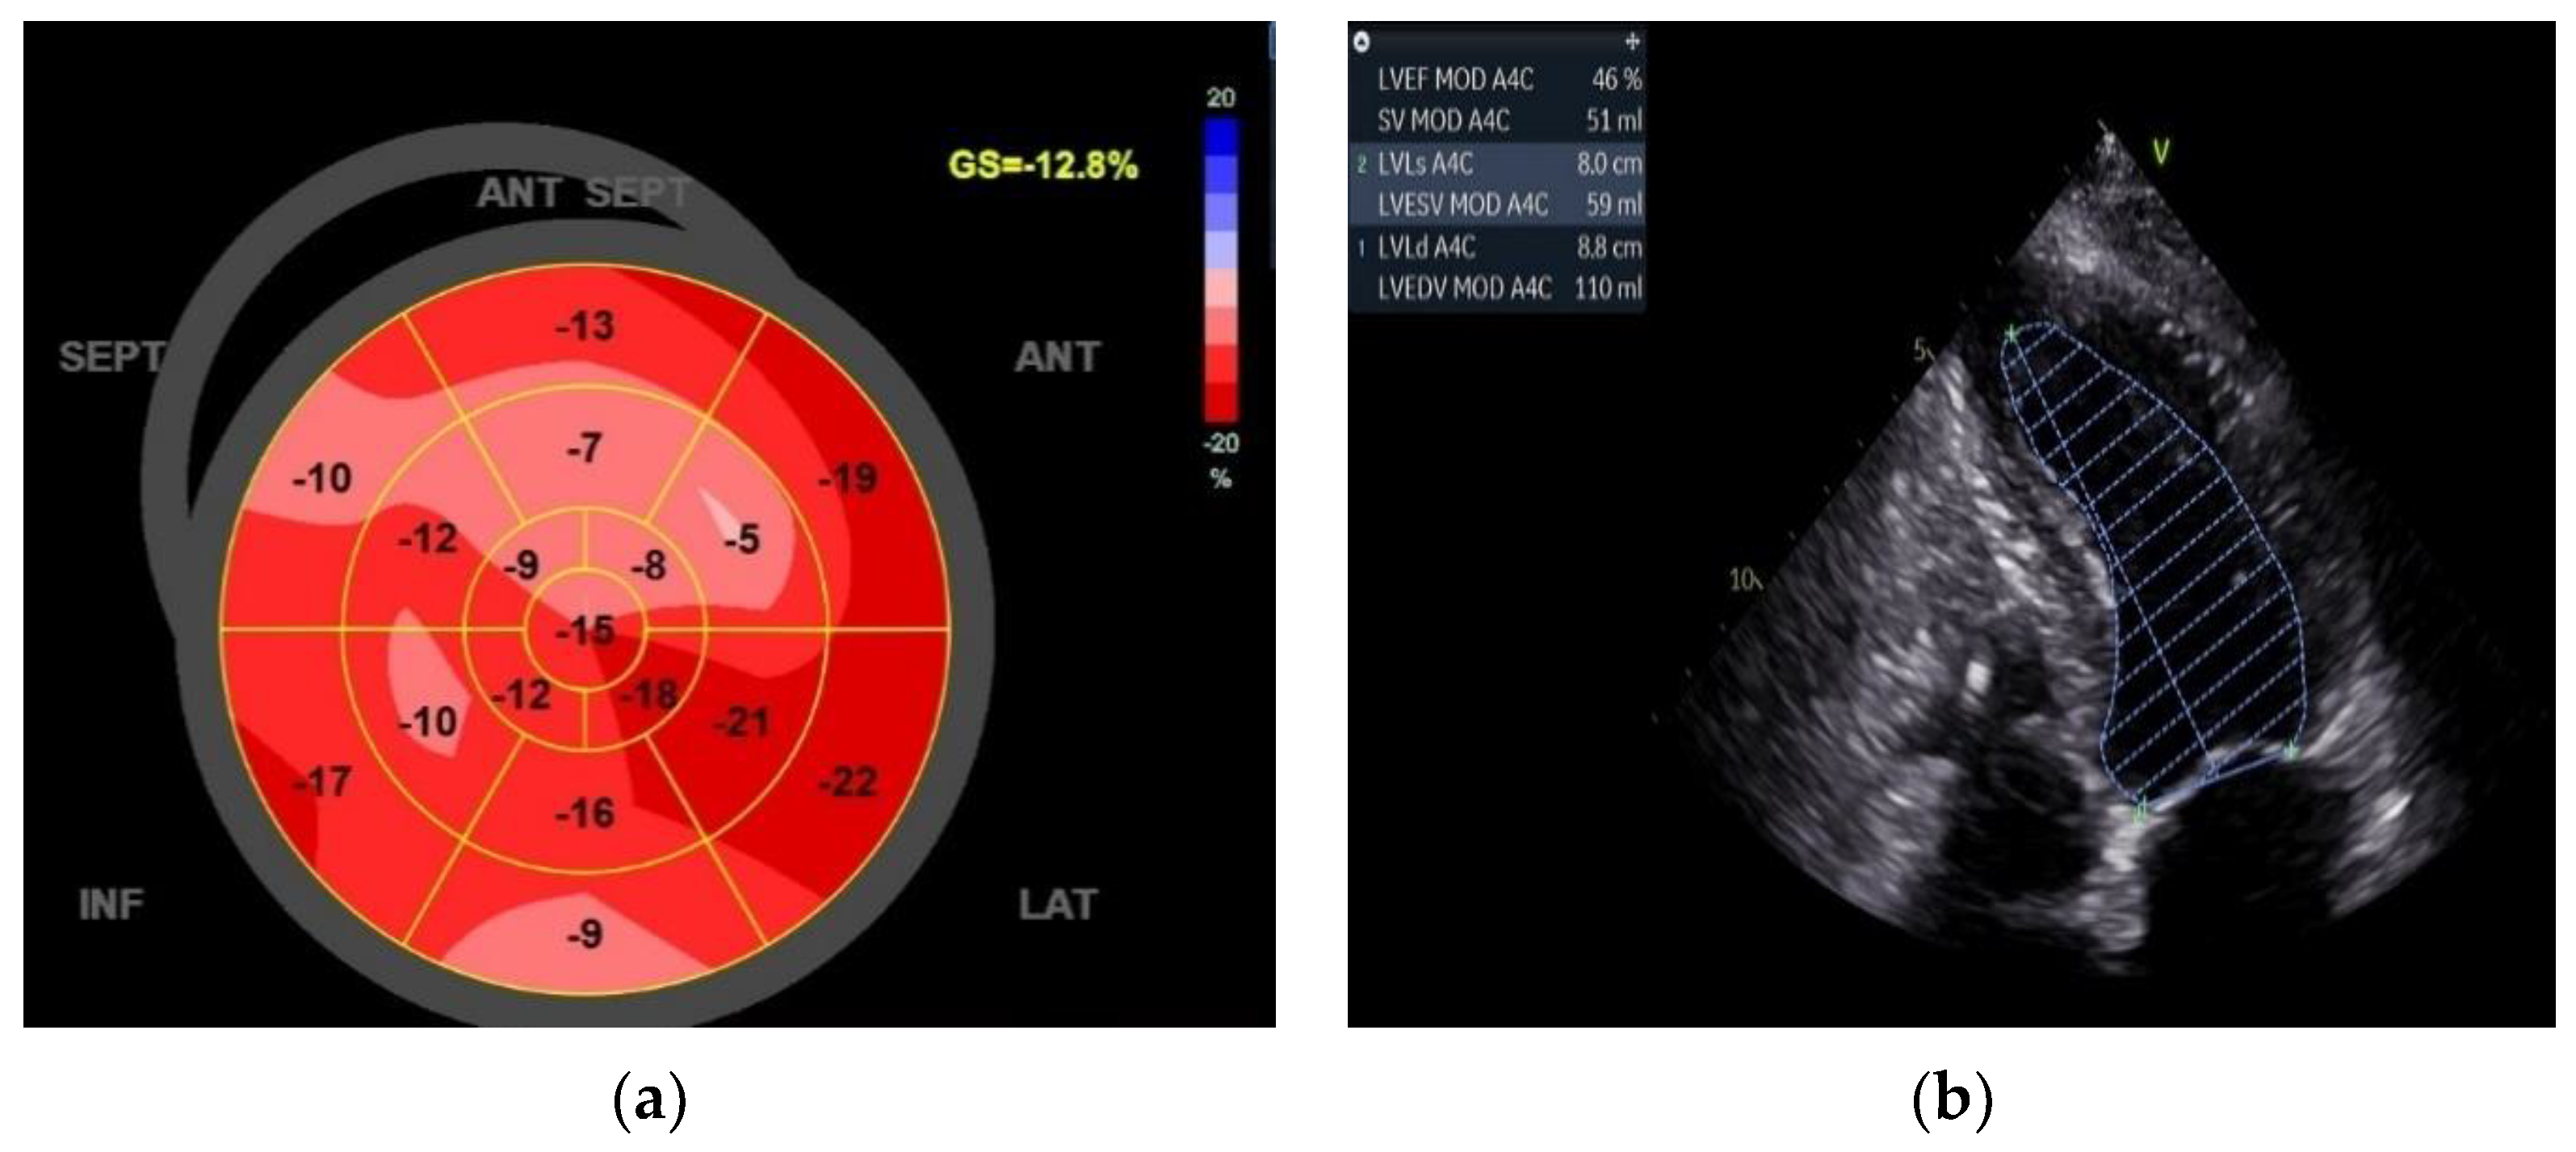

However, the improvement in quality of life (QoL) was followed by the ECO graphic exam, which shows impressive data with an EF of 46% and a GLS of -12.8%. (Figure 4)

Figure 4. Three months of echocardiographic data: (a) GLS of -12.8%; (b) EF of 46%.